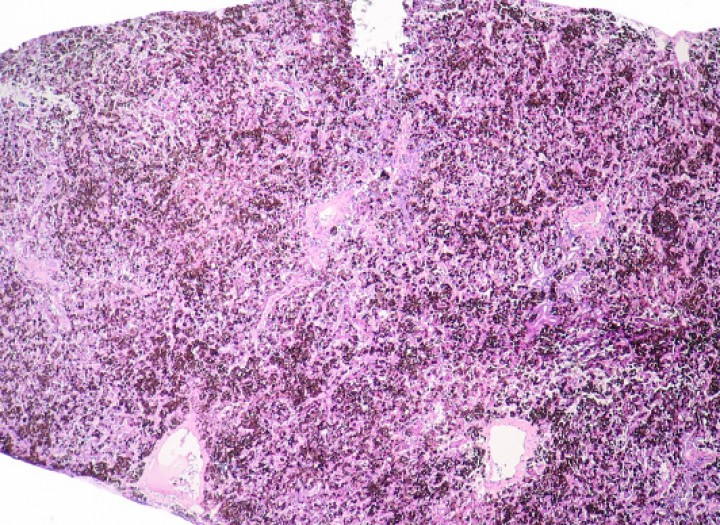

Se observaron 8 neoplasias, diagnosticadas en 6 de los 131 (4,6%) anfibios. Dos correspondían a adenocarcinomas sin evidencias de metástasis: uno intestinal en una rana dardo verdinegra (Dendrobates auratus) (Fig. 8), y otro en un tejido no identificable en un sapo buey (Rhinella schneideri); este último mostraba, además, hemangiomas en el pulmón (Fig. 9). El adenocarcinoma intestinal de la rana dardo verdinegra (Dendrobates auratus) consistía en una proliferación mal delimitada y no encapsulada de enterocitos que formaban criptas y glándulas variablemente dilatadas o, raramente, nidos diminutos compactos que invadían de forma amplia todas las capas del segmento intestinal afectado (Fig. 8) y mostraban anisocitosis, anisocariosis, pleomorfismo y anaplasia bajos a moderados, sin actividad mitótica aparente. Otros 3 anfibios padecieron neoplasias hematopoyéticas: un linfoma multicéntrico con componente epiteliotrópico en una rana tomate (Fig. 10) y dos neoplasias de células redondas no identificables de forma clara mediante la tinción rutinaria en un sapillo balear (Alytes muletensis) y un axolote (Ambystoma mexicanum). Otro sapillo balear (Alytes muletensis) mostraba una proliferación multicéntrica benigna de epitelio renal tubular (Fig. 11) organizado en estructuras tubulares, papilares y quísticas (Fig. 12), compatible con adenomatosis renal (adenomas múltiples); se observó atipia celular en escasas células neoplásicas y en células epiteliales de túbulos no neoplásicos. Adicionalmente, en este sapillo balear (Alytes muletensis) se apreció un foco hepático bien delimitado y no encapsulado de proliferación de hepatocitos compatible con hiperplasia nodular o un hepatoma; la ausencia de tríadas portales dentro de esta neoplasia es compatible con un hepatoma (Fig. 13).

<p>Piel; rana tomate (<em>Dyscophus guineti</em>). Con patrón difuso, la dermis (d) está densamente infiltrada por linfocitos pequeños neoplásicos acompañados por detritos nucleares; estos infiltrados forman además numerosos focos de epiteliotropismo caracterizados por la presencia de múltiples linfocitos dispuestos en pequeños nidos intraepidérmicos (cabezas de flecha). e: epidermis. Hematoxilina-eosina, x220.</p>

Figura 10

Piel; rana tomate (Dyscophus guineti). Con patrón difuso, la dermis (d) está densamente infiltrada por linfocitos pequeños neoplásicos acompañados por detritos nucleares; estos infiltrados forman además numerosos focos de epiteliotropismo caracterizados por la presencia de múltiples linfocitos dispuestos en pequeños nidos intraepidérmicos (cabezas de flecha). e: epidermis. Hematoxilina-eosina, x220.